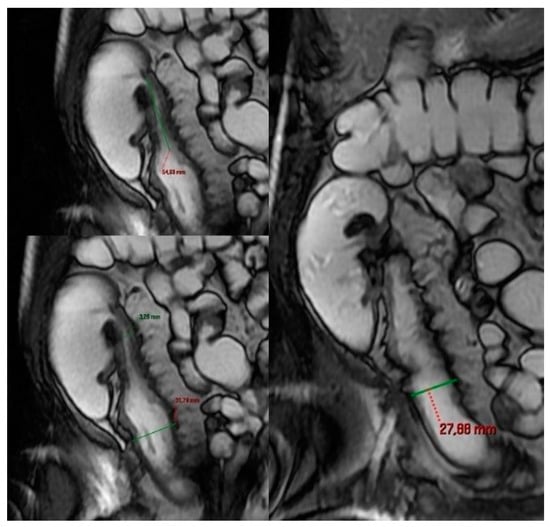

- Cronin, C.G.; Delappe, E.; Lohan, D.G.; Roche, C.; Murphy, J.M. Normal small bowel wall characteristics on MR enterography. Eur. J. Radiol. 2010, 75, 207–211. [Google Scholar] [CrossRef]